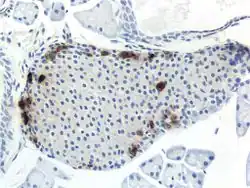

A pancreatic islet, stained. -

A pancreatic islet, showing alpha cells -

A pancreatic islet, showing beta cells.